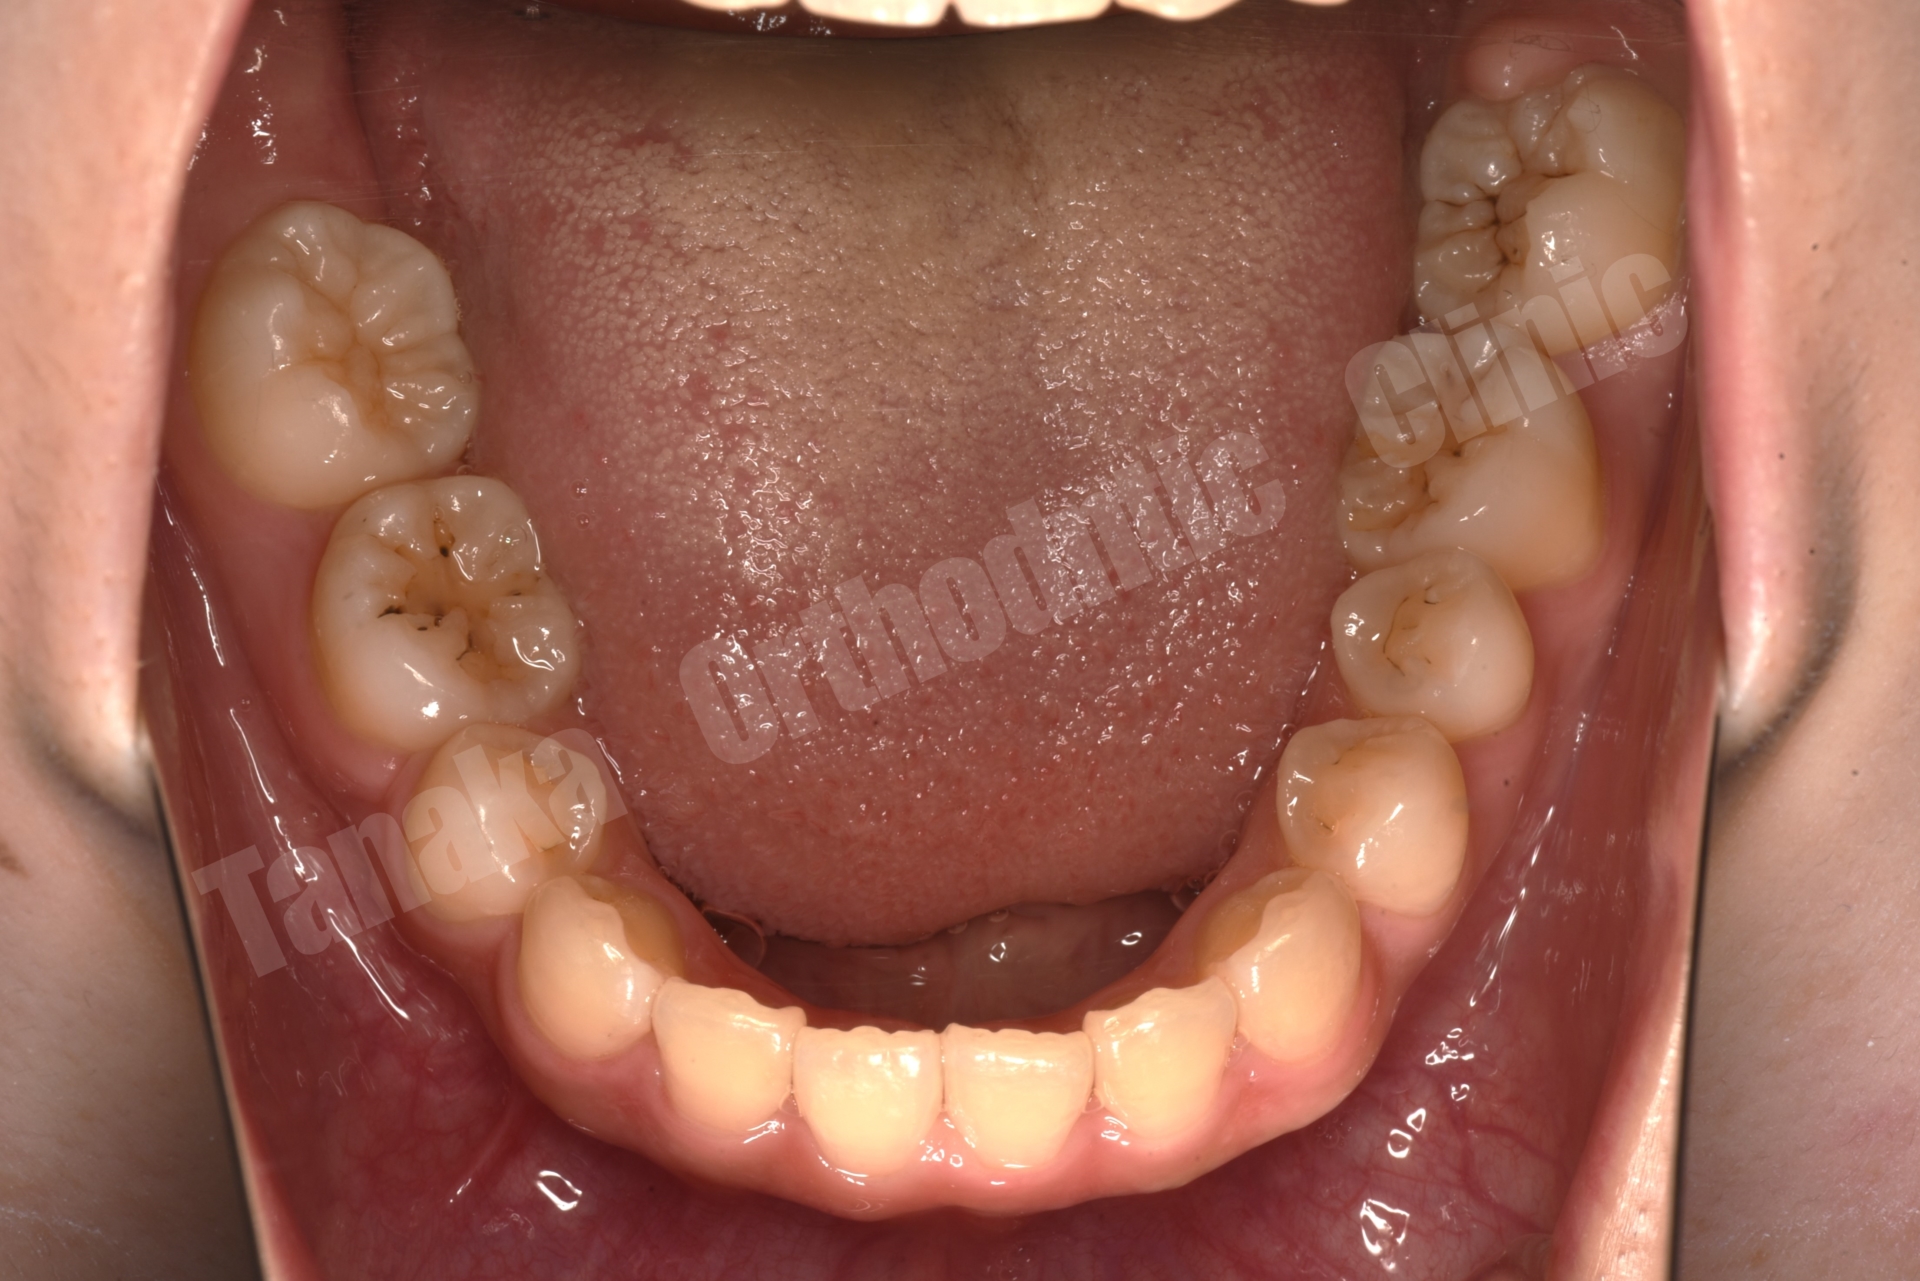

初診時の診査では、上顎前歯が唇側に傾斜しており、前歯の水平被蓋(オーバージェット)が大きい状態でした。そのため口元の突出感が認められ、前歯部は十分に噛んでいない状態でした。また下顎正中は左側へ偏位しており、右下E(乳臼歯)の残存と5番の先天欠如、さらに下顎両側7番の位置異常も確認されました。さらに患者様は10代半ばの頃に一度、非抜歯でマルチブラケット矯正を受けており、その影響もあって上顎中切歯には歯根吸収が生じ、歯根がやや短くなっている所見も認められました。

そこで治療では上下歯列に唇側マルチブラケット装置を装着し、歯列全体の排列を行いました。上顎前突を改善するため上顎両側4番を抜歯し、前歯を後退させて口元のバランスを整える計画としました。さらに下顎正中の改善のため右下Eを抜歯し、約11mmある乳臼歯部のスペース閉鎖を行う計画としました。このスペース閉鎖には矯正用アンカースクリューを使用し、右側6番・7番を近心移動させる必要があります。また治療途中で萌出してくる右下7番の位置を適切にコントロールすることも重要なポイントとなります。